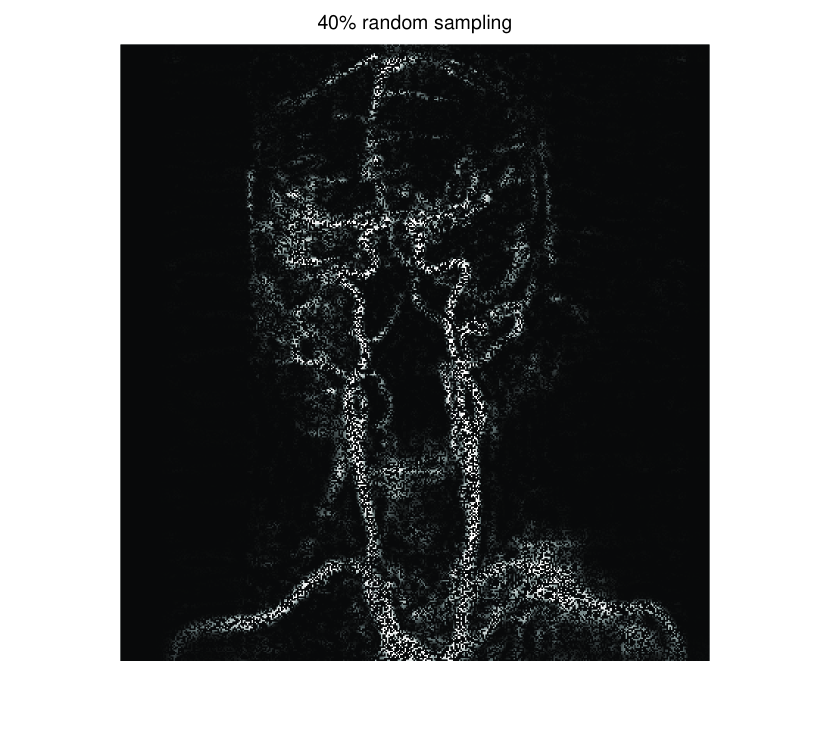

In this section, we first present numerical results of ISVTA for matrix completion problems, and then compare it with some state-of-art methods (singular value thresholding algorithm (SVTA) and singular value projection algorithm (SVPA) respectively proposed in [11] and [31]) for image inpainting problems. Numerical experiments on matrix completion problems show that our method performs powerful in finding a low-rank matrix and the numerical experiments about image inpainting problems show that our algorithm has better performances than SVTA and SVPA. Among all of the experiments, differing from the Scheme 2, we set , and

5.2 Image inpainting

In this subsection, we demonstrate performances of ISVTA on image inpainting problems. The ISVTA is tested on some medical grace images ( Brain angiography image (BAI), Hand angiography image (HAI) and Intracranial venous image (IVI)). We use the SVD to obtain their approximated low-rank images with rank , respectively. Numerical results of ISVTA for theses low-rank image inpainting problems are reported in Table 5, 6, 7, 8.

Table 5, 6 show that ISVTA performs powerful in finding a low-rank matrix on image inpainting problems. Indeed, we could get an exact low-rank image by the ISVTA by choosing proper . Moreover, it is necessary to point out that our method does not work well for all , and we can find that is not a good strategy for the low-rank IVI either or . The numerical results of ISVT, SVTA and SVPA compared in Table 5, 6, 7, 8, 9, 10 under same circumstance show that the ISVT algorithm performs far more better than ISTA and SVPA on image inpainting problems for some proper .